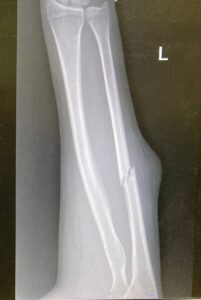

Нику окружила и избила толпа разъяренных мужчин, прятавших свои лица под повязками. Из-за полученных травм ей потребовалась госпитализация. Второй женщине тоже потребовалась медпомощь — ей пришлось наложить гипс.

«Эта маленькая деревушка состоит домов из шести, и она окружена колючим забором. Они прошли через этот забор, и мы с ними оказались в замкнутом пространстве внутри. У нас оставался путь бежать вверх по камням, что было сложно, или через забор. Вторая активистка среагировала быстрее, она побежала в сторону забора и пробежала мимо поселенцев, они успели ударить ее по руке и по голове, сломали ей руку, но она смогла убежать в сторону машины волонтера-координатора», – восстанавливает события Ника.

«У меня три раны на голове, на которые наложены пять швов, – говорит Ника. – У меня синяки на ногах, на руках, на ребрах и спине».